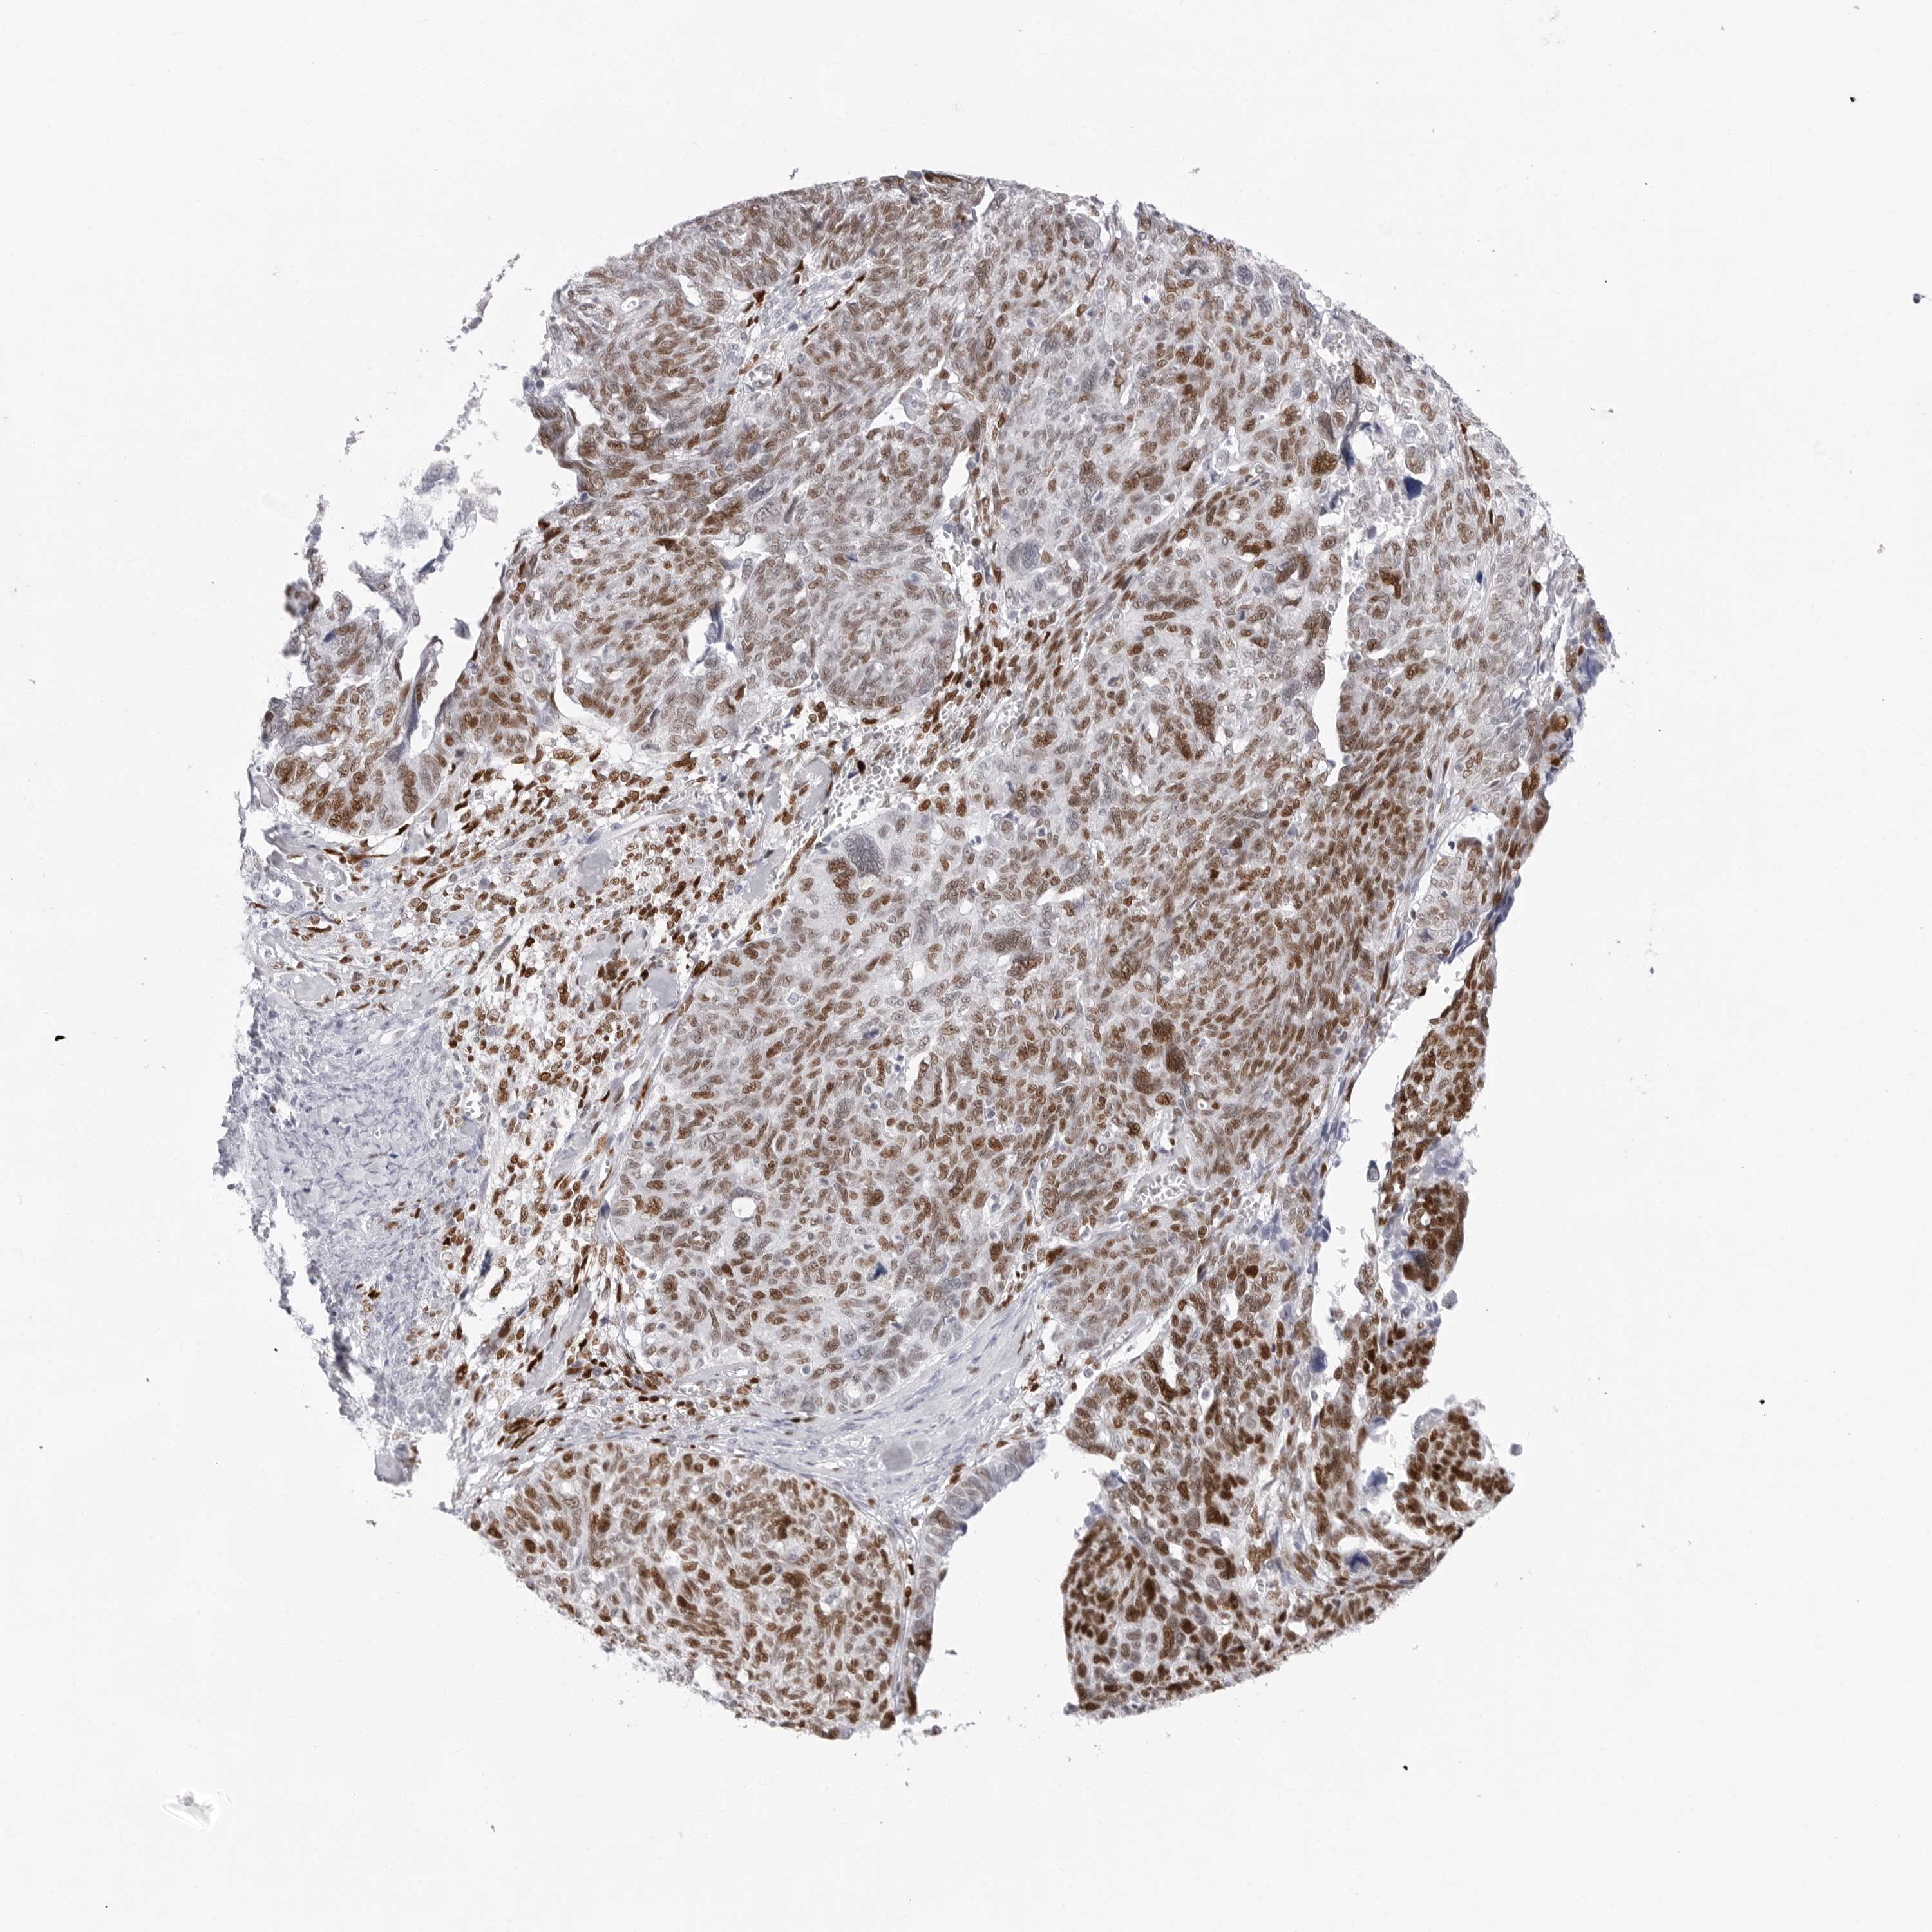

OVARIAN CANCER - Protein expressioni

A mouse-over function shows sample information and annotation data. Click on an image to view it in a full screen mode. Samples can be filtered based on level of antibody staining by selecting one or several of the following categories: high, medium, low and not detected. The assay and annotation is described here.

Note that samples used for immunohistochemistry by the Human Protein Atlas do not correspond to samples in the TCGA dataset.

Antibody stainingi

Antibody staining in the annotated cell types in the current human tissue is reported as not detected, low, medium, or high, based on conventional immunohistochemistry profiling in selected tissues. This score is based on the combination of the staining intensity and fraction of stained cells.

Each image is clickable and will lead to virtual microscopy that enables deeper exploration of all samples and also displays staining intensity scores, fraction scores and subcellular localization as well as patient and tissue information for each sample.

Antibody HPA028136

Antibody HPA030518

Antibody HPA030520

Staining

High

Medium

Low

Not detected

Cystadenocarcinoma, serous, NOS

Carcinoma, endometroid

Cystadenocarcinoma, mucinous, NOS

Carcinoma, NOS